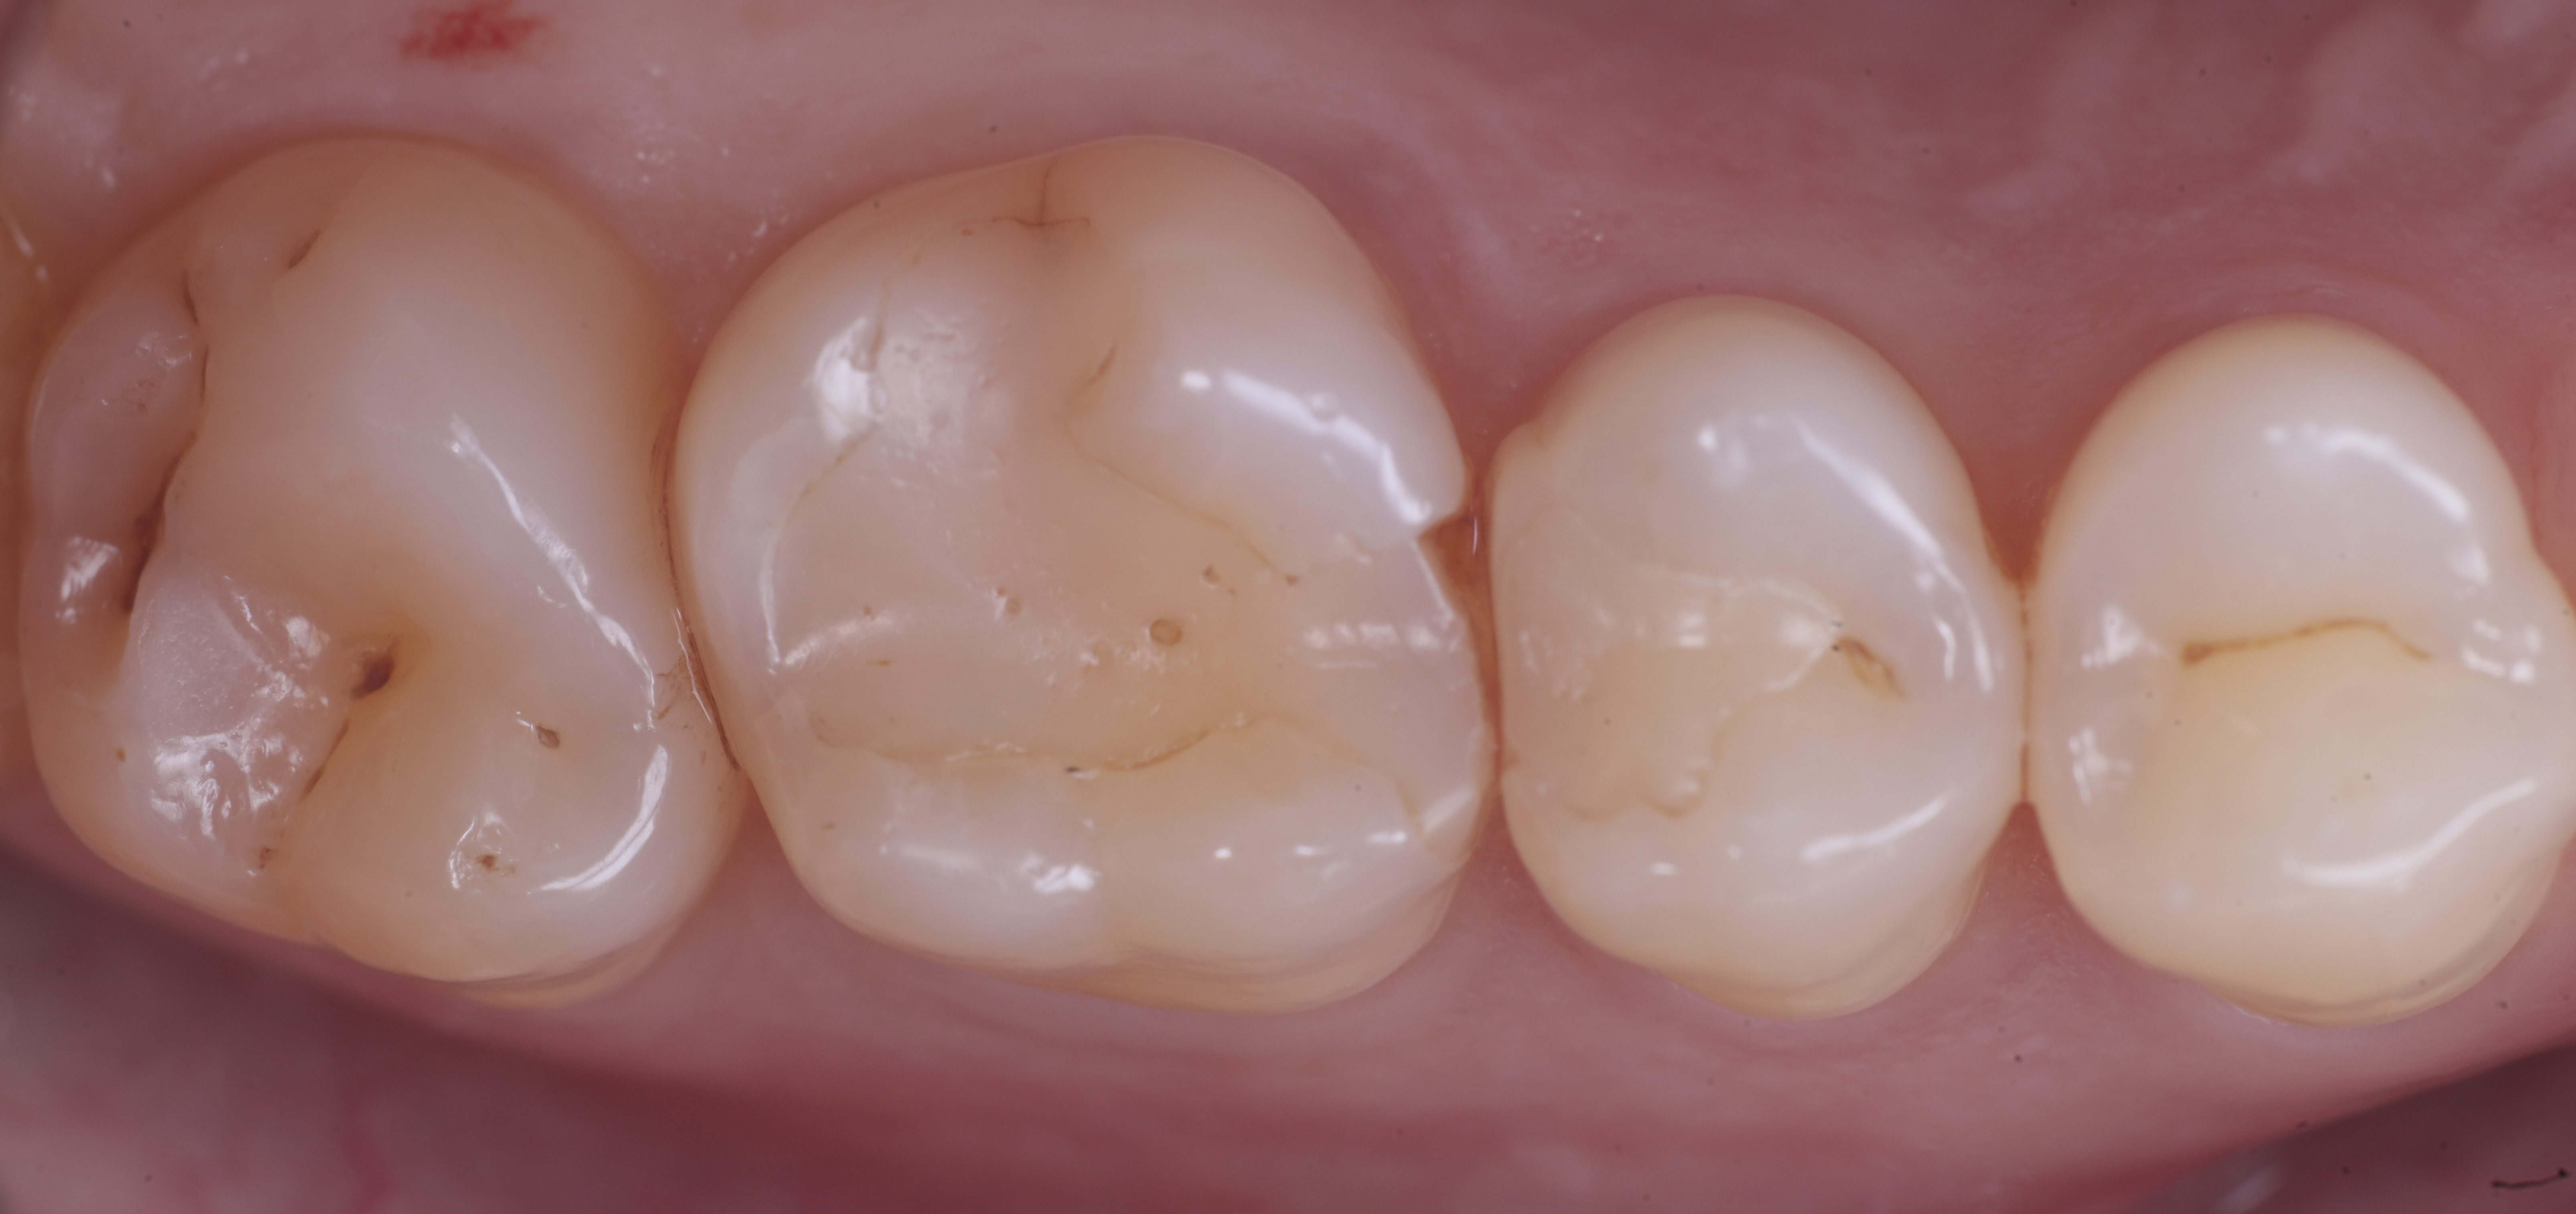

foto 11 Restauri ultimati sotto controllo occlusale

foto 8 Modellazione ed aspetto occlusale

foto 9 Modellazione ed aspetto vestibolare

foto 10 Modellazione ed aspetto palatino